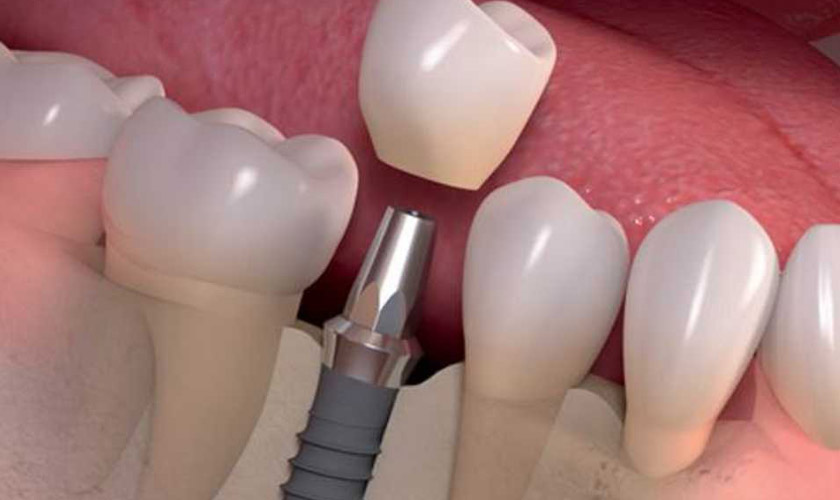

Implant là trụ cấu thành từ Titanium, được cấy vào xương hàm nhằm mục đích thay thế chân răng đã mất. Sau thời gian lành thương và implant đã tích hợp vào xương, Bác sĩ sẽ tiến hành gắn răng sứ trên implant để tạo thành một chiếc răng hoàn chỉnh nhất.